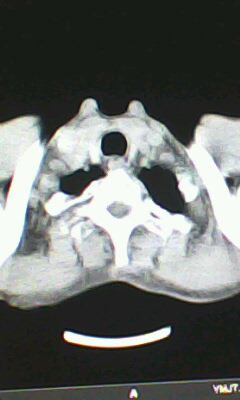

胸廓呈桶状,双膈低平,肺实质及纵隔未见明显异常密度灶考虑肺气肿.

未见明显异常。

未见明确异常。

做个肺功能检查。肺ct无明显异常。